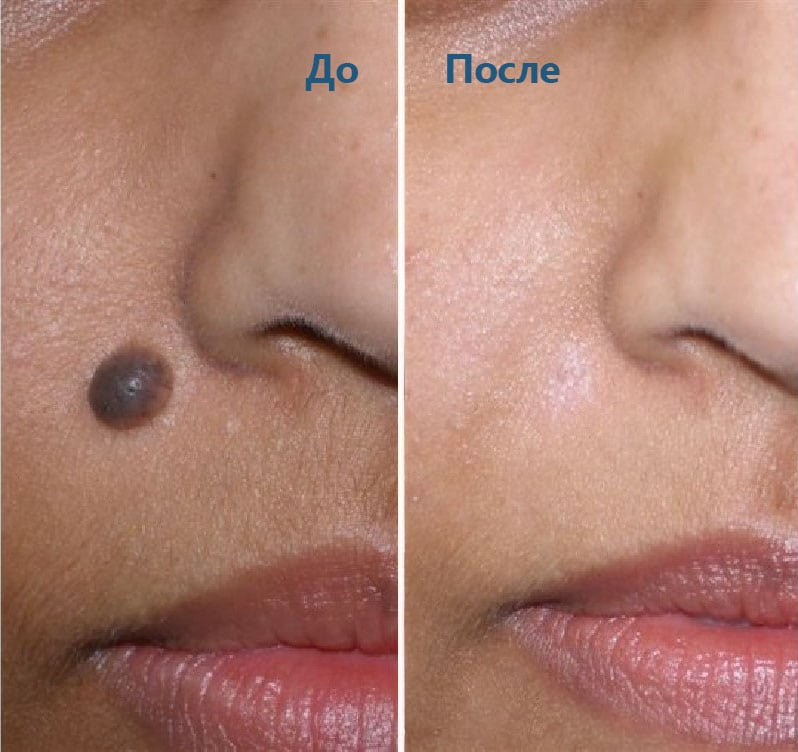

Фото: лазерное удаление

В его основе лежит воздействие лазерным лучом на тело папилломы. При помощи сверхкоротких последовательных волновых импульсов и происходит очищение кожи. Здоровый участок при этом не повреждается.

- При деструкции наростов диаметром более 5 мм на коже может остаться небольшое пятнышко, которое исчезнет со временем.

- Процесс заживления эпидермиса может занять около недели.

- Лазерное удаление широко применяется для удаления бородавок на лице, подмышками, а также в интимных местах.

Процедура признается высокоэффективной и безболезненной.

Фото: после лазеротерапии